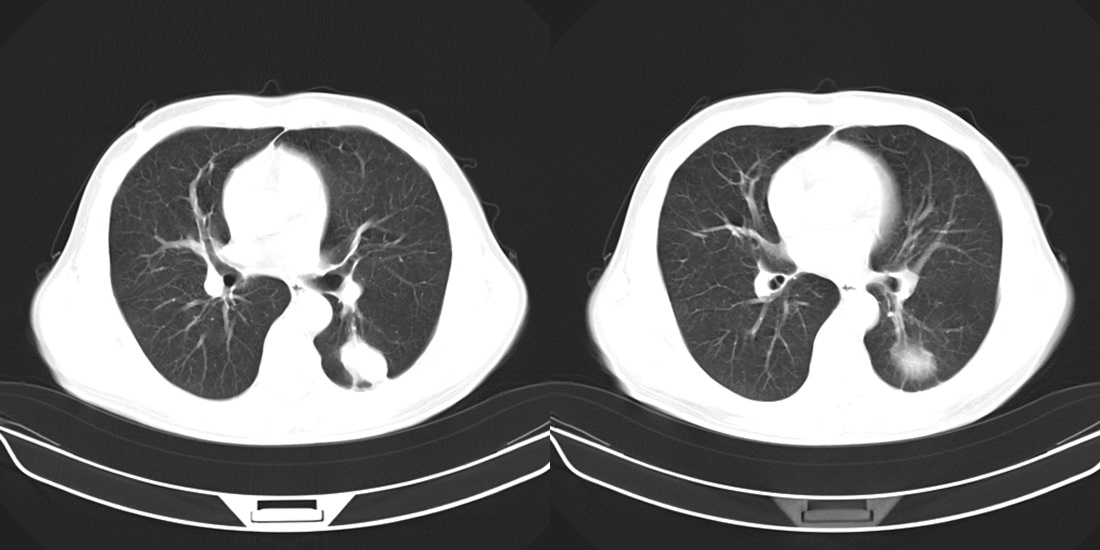

标题: CT10251:男性56岁,结核球? [打印本页]

标题: CT10251:男性56岁,结核球?

56岁男性,低热、消瘦,曾x线诊断肺结核。

两肺结核,左肺结核球。

双肺结核伴左上肺结核球形成

两肺多形性病变,支持肺结核.

两肺多形性病变,且在结核好发部位。支持肺结核.